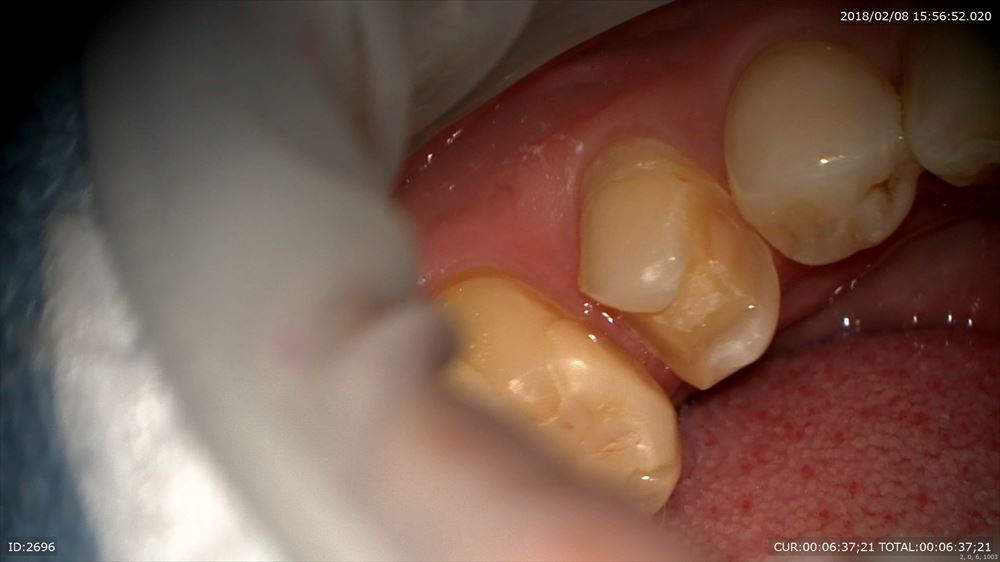

この方は型とり

先程の方もこの方もマイクロスコープを使用し出血がありません。

もちろん無痛。